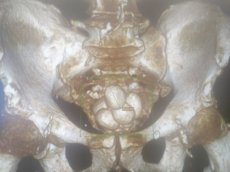

74-річного чоловіка госпіталізували у важкому стані. Лікарі діагностували низку хвороб, частина з яких у запущених стадіях: доброякісна гіперплазія передміхурової залози, хронічна затримка сечі, множинні камені сечового міхура, двобічний уретерогідронефроз, гостра ниркова недостатність.

Першим етапом виконано цистолітотомію з епіцистостомією. Пацієнту забезпечили відтік сечі через спеціальну трубку, адже природній спосіб уже був неможливий. Далі лікарі приступили до видалення каменів великих розмірів, якими був наповнений сечовий міхур пацієнта (аж 12). Лапароскопічний спосіб у даному випадку був неможливим. Тож лікарі провели відкриту операцію.

Другим етапом (після нормалізації роботи нирок та усунення гострої ниркової недостатності) стала трансуретральна резекція передміхурової залози (золотий стандарт лікування гіперплазій простати, без розрізу, через природні сечовивідні шляхи). Об'єм простати, враженої доброякісною пухлиною, сягав гігантських розмірів - 100 см кубічних, при нормі – 30-35 см куб.